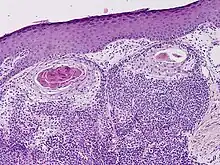

Clear cell hidradenocarcinoma

Hidradenocarcinoma (also known as malignant hidradenoma, malignant acrospiroma, clear cell eccrine carcinoma, or primary mucoepidermoid cutaneous carcinoma) is a malignant adnexal tumor of the sweat gland. It is the malignant variant of the benign hidradenoma. It may develop de novo or in association with an existent hidradenoma.[1]